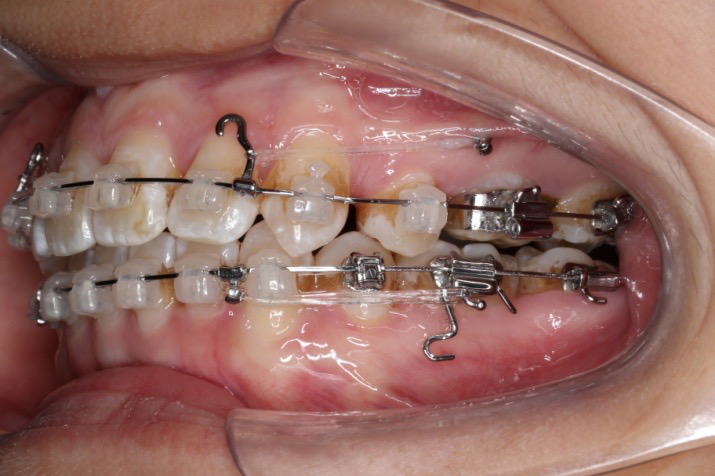

2016.10.31  初戴,0.013cu-niti2017.1.13  上颌加TPA,U56间斜形植入韩国庆北1312-08种植钉,上下0.16cu-niti

2017.02.16  上下0.014*25 cu-niti,50g 拉尖牙远中

2017.04.28

2017.04.28  上0.016*25ss 13、23近远中约5度 v形曲,下0.017*25ss

2017.05.26  磨牙近中倾斜,下颌36、46加power arm

2017.07.25

2017.07.25  上前牙加颈部弹力线